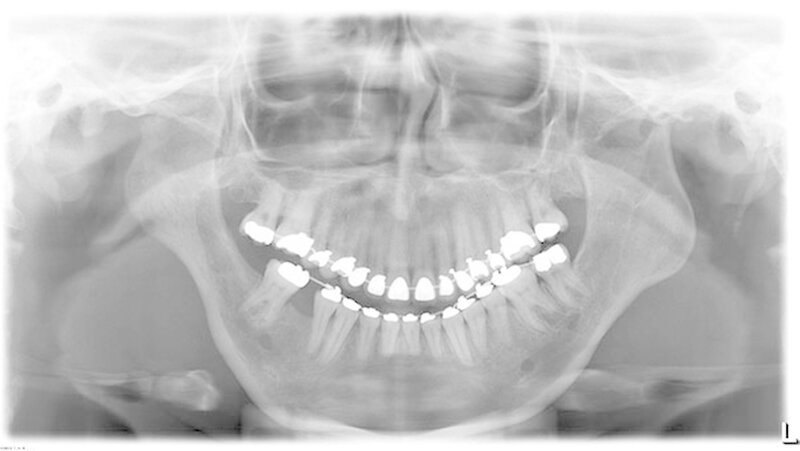

Die Patientin war gerade über 20 Jahre alt, als die Krankheit schleichend begann: Zunächst fiel der jungen Frau auf, dass der Kontakt zwischen den oberen und den unteren Schneidezähnen immer mehr verloren ging. Mit der Zeit wurde die Lücke immer größer, was im weiteren Verlauf ein Abbeißen unmöglich machte. Zudem bemerkte sie, dass ihr Kinn immer fliehender wurde, also immer weiter zurückfiel.

Daraufhin wurden eine kieferorthopädische Behandlung mit einer festsitzenden Spange und nacheinander zwei Operationen zur Umstellung des Ober- und Unterkiefers durchgeführt. Diese ersten Operationen konnten jedoch die weiter zunehmende Abweichung des Unterkiefers nach hinten und damit auch den offenen Biss nicht stoppen.

Das Bonner MKG-Chirurgenteam um Prof. Dr. Dr. Rudolf Reich diagnostizierte eine zunehmende Einschmelzung (Resorption) der Kiefergelenkfortsätze, wodurch die gesamte Abstützung des Unterkiefers am Schädel verloren gegangen war.